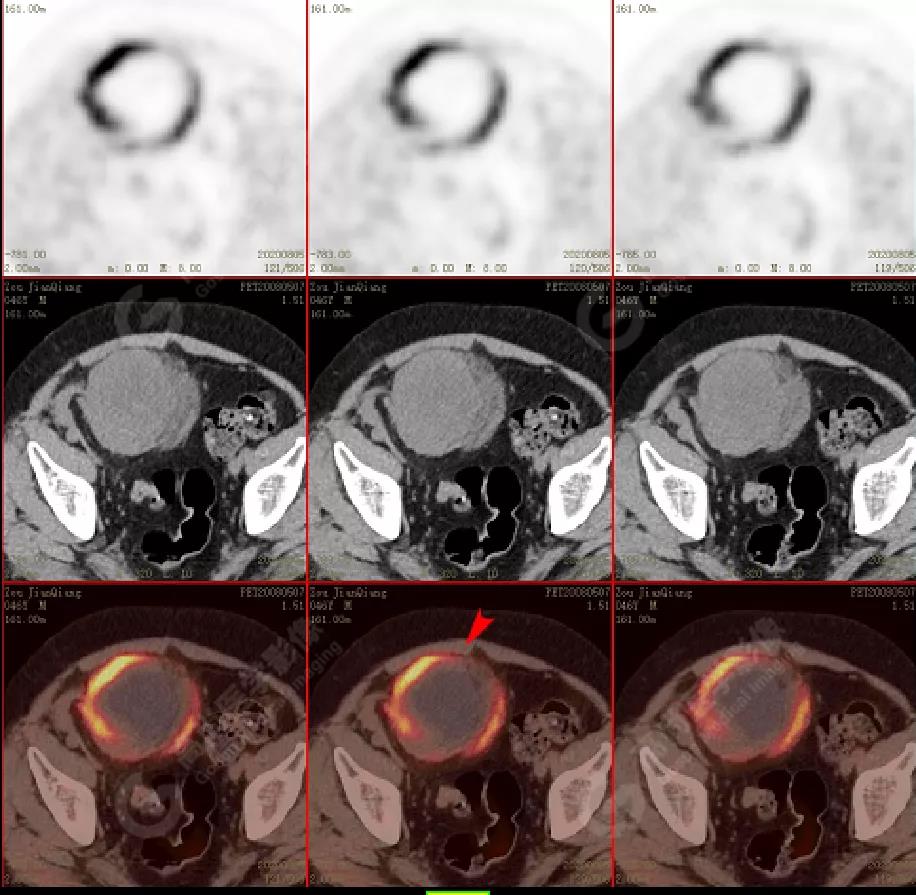

PET/CT檢查

↑移植腎下部等密度腫塊,代謝環(huán)狀增高,SUVmax13.4,中心代謝缺損